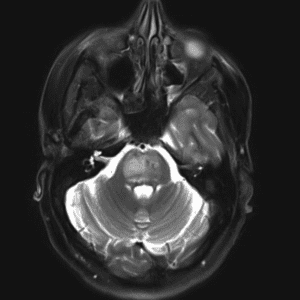

Brain Tumor Practice Cases

Case #4

Focal cortical dysplasia (type II)